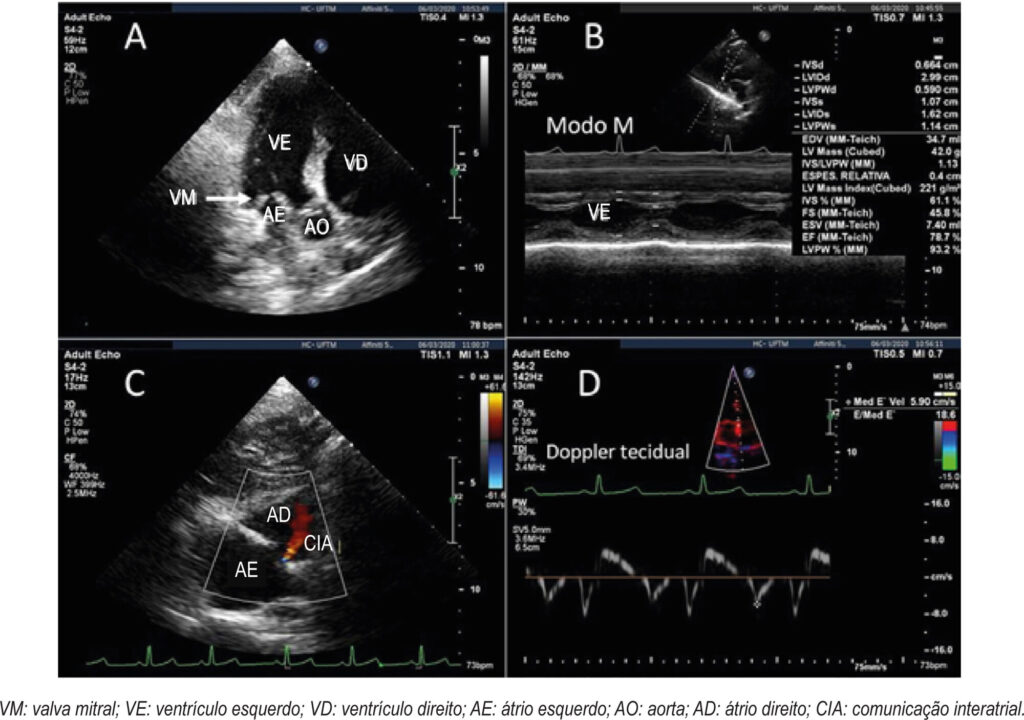

Mucopolissacaridoses IV e VI: Aspectos ao Ecocardiograma Bidimensional com Strain pelo Speckle Tracking em uma Série de Casos

As Mucopolissacaridoses (MPSs) pertencem ao grupo das doenças de depósito lisossômico associadas à deficiência parcial ou total de 11 diferentes hidrolases lisossômicas responsáveis pela degradação dos Glicosaminoglicanos (GAGs). O acúmulo desses GAGs pode comprometer as válvulas, o miocárdio e os vasos coronários. As formas que acumulam sulfato de dermatan (MPS I, II, VI e VII) estão associadas com espessamento valvar (E>D). Além disso, as MPSs são consideradas uma das causas mais comuns de espessamento do anel mitral na infância. O comprometimento cardíaco ainda inclui hipertrofia, encurtamento das cordas tendíneas e espessamento dos músculos papilares. O ecocardiograma é uma técnica essencial para avaliação do comprometimento cardíaco nas MPSs. O estudo da deformação miocárdica (strain) pelo Speckle-Tracking Bidimensional (2D-STE) confere avaliação mais sensível da deformação da fibra miocárdica, revelando acometimento do miocárdio precoce e subclínico, independentemente de alterações da Fração de Ejeção do Ventrículo Esquerdo (FEVE).,

Esta série de casos revisa aspectos ecográficos relevantes do acometimento cardíaco, complementados pela técnica do 2D-STE em três pacientes com MPS em seguimento ambulatorial e em uso de Terapia de Reposição Enzimática (TRE).